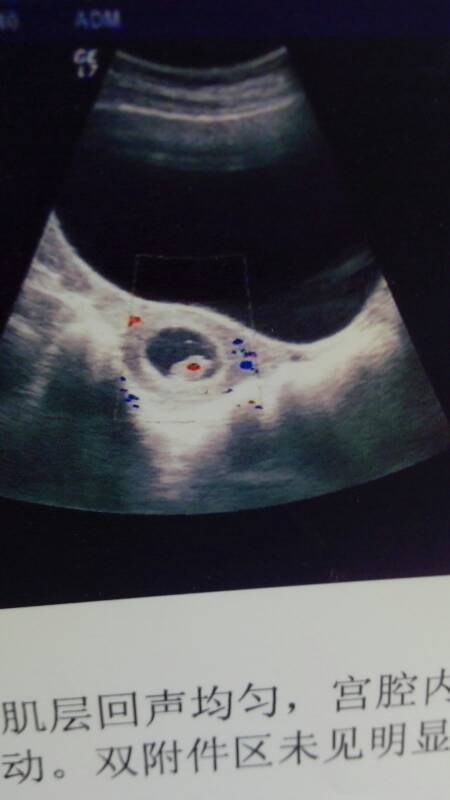

那么问题来了,我的孕囊是长的还是圆的啊╮(╯3╰)╭

孕囊圆和长根本不能辨别胎儿性别!我妹妹怀他儿子我还专门看了他的孕囊!是很圆!我看了好多医学的书!说的一般正常的孕囊都是圆的!如果有张过囊中或者做过人流!怀宝宝的时候孕囊就有可能成长条

圆圆的…………